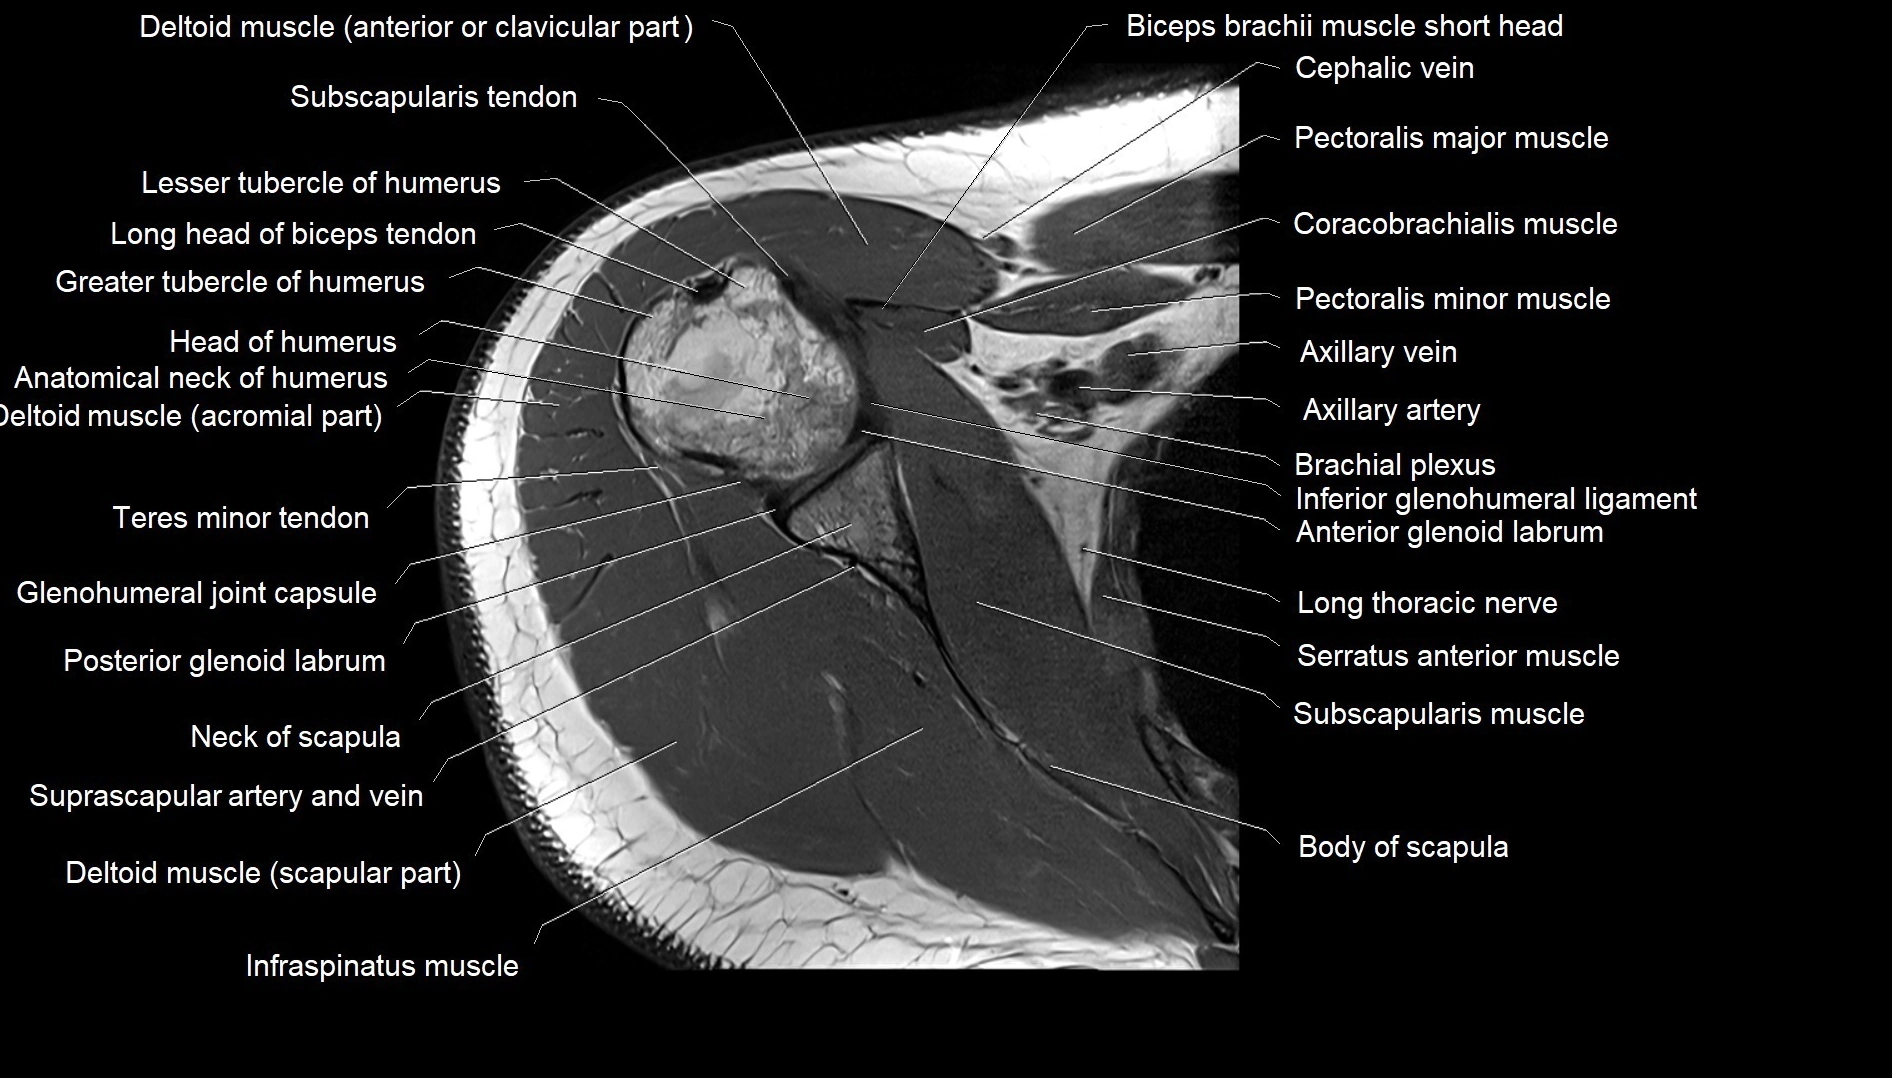

CT image

image